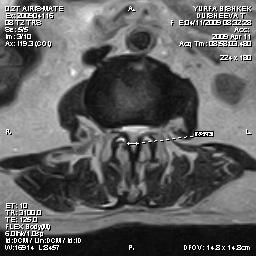

типы СПК. Во всех случаях позвоночный канал

был сужен: центральный стеноз имел место у 25 больных (56,8%) с переднезадним

размером меньше 10±0,05 мм, при поперечном размере не более 15 мм см рис ;

латеральный стеноз с размерами латерального рецессуса менее 3±0,07 мм

из-за гипертрофии дугоотросчатых суставов у 11 (25%) больных см рис №2.

Рис.2.МРТ: центральный

стеноз. Рис.3. МРТ:

латеральный стеноз на фоне

артроза левого дугоотросчатого сустава.